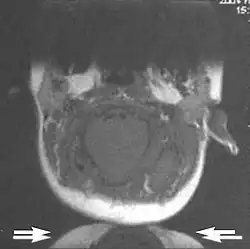

Wrap-around

A wrap-around artifact also known as an aliasing artifact, is a result of mismapping of anatomy that lies outside the field of view but within the slice volume.[4] The selected field of view is smaller than the size of the imaged object. The anatomy is usually displaced to the opposite side of the image (Figs 6 and 7). It can be caused by non-linear gradients or by undersampling of the frequencies contained within the return signal.[1] The sampling rate must be twice the maximal frequency that occurs in the object (Nyquist sampling limit). If not, the Fourier transform will assign very low values to the frequency signals greater than the Nyquist limit. These frequencies will then ‘wrap around’ to the opposite side of the image, masquerading as low-frequency signals. In the frequency encode direction a filter can be applied to the acquired signal to eliminate frequencies greater than the Nyquist frequency. In the phase encode direction, artifacts can be reduced by an increasing number of phase encode steps (increased image time). For correction, a larger field of view may be chosen.[1]